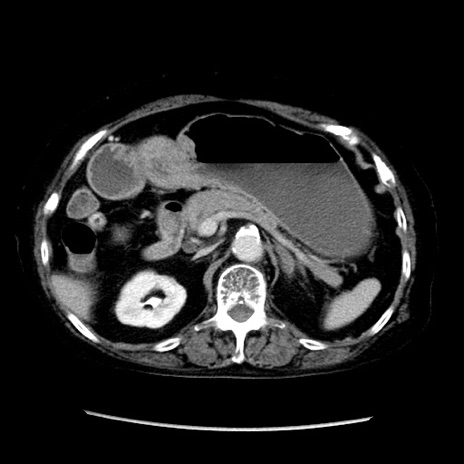

症例14(横断像)

【症例】 90歳代女性

【主訴】 腹痛・嘔吐

【現病歴】今朝から左側腹部痛を認めた。 経過観察していたが、嘔吐を認めたため来院。

【既往歴】 子宮癌術後

【身体所見】 意識清明、BP 127/54mmHg、P 98bpm Sp02 95%(RA)、BT 35.8°C、腹部平坦・軟腸ぜん動音聴取良好、右下腹部圧痛(+) 反跳痛なし

【データ】WBC 9800、CRP 0.46